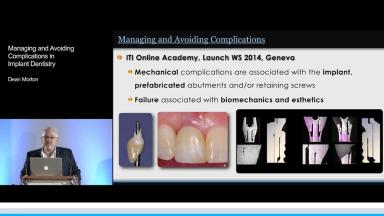

Dean Morton discusses how to plan for success rather than failure and how to effectively manage problems when they occur.

The presenter emphasizes how team members must be able to manage the worst possible complications, which may require adding another member to the team who can manage the problem. Avoiding complications means embracing teamwork, a multidisciplinary approach, and effective communication amongst treatment providers to optimize patient care.

The etiology of tooth loss and the goals of therapy provided by the implant clinician are also covered. The lecture includes excellent use of clinical cases to highlight common complications in implant dentistry to include biological, mechanical, and technical complications and how to avoid them.

The lecture concludes with a discussion of careful planning and execution as the keys to successful treatment outcomes over an extended period of time.